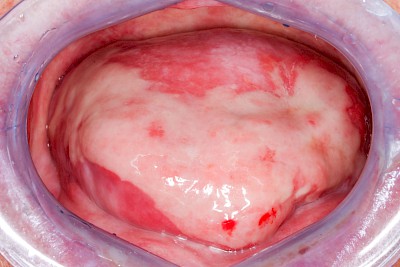

Kauen auf Wange, Zunge & Lippen

Das Kauen auf Wange, Zunge oder Lippen zählt zu den sogenannten Habits und ist meist stressbedingt. Diskrete Linien (Verhornungsleisten) oder aber unruhige Schleimhautareale bis hin zu Erscheinungsformen wie "wildes Fleisch" können dabei auffallen.

Beispiele32 Bilder